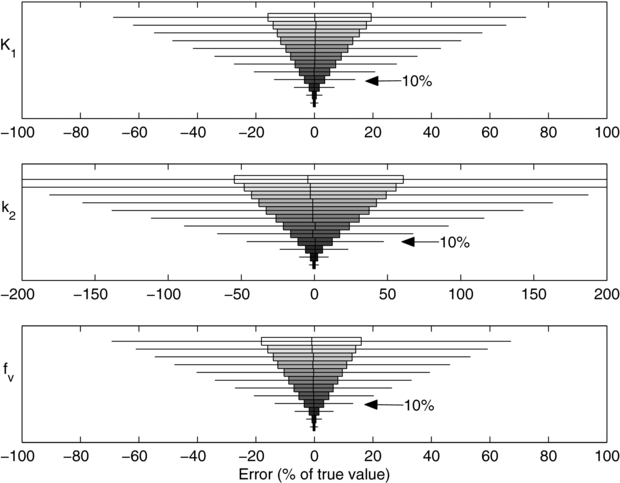

As shown in figure 2, the parameter estimates had low biases, i.e. bars are centred near zero error, and variances, i.e. the widths of the bars, decrease with noise level. The bias of K1, was less than 1% of the true value with noise levels up to 20% SD. The bias at the highest noise level (50% SD) was (3.4 ± 0.4)% of the true value (99% CI). This indicated that our noisy simulations and parameter estimates behaved as expected and that there was no evidence of programming errors.

Figure 2. Distribution of errors in the estimated parameter value at 12 noise levels and simulated using uniform, 5 s frames. The noise levels are, from top to bottom, 50%, 45%, 40%, 35%, 40%, 25%, 20%, 15%, 10%, 5%, 2% and 1%. A noise level of 10%, noted with arrows, is typically observed in clinical data. Filled boxes: interquartile range (IQR); whiskers: ±1.5 · IQR; vertical hash: mean; outliers not shown.

Standard image High-resolution imageTo determine an appropriate noise level for subsequent simulations, we analysed the cardiac phantom data described in section 2.2. Volumes of interest were drawn in the cardiac insert portion of the phantom, corresponding to single image voxels (0.01 mL), and small, average and large segments (1.7, 3.5 and 5.0 mL) in a standard 17-segment cardiac model (Cerqueira 2002), as well as the entire LV myocardium (64 mL). As expected, image noise decreased smoothly with an increase in the number of coincidences or region size, figure S2 (available from stacks.iop.org/PMB/58/5783/mmedia). For subsequent simulations, we chose a noise level ξ = 0.1 which, when applied following (7), gave simulated TACs with a frame SD in the range of 4% (for a 15 s frame at 120 s) to 15% (for a 1 s early frame or a 15 s frame at 6 min).